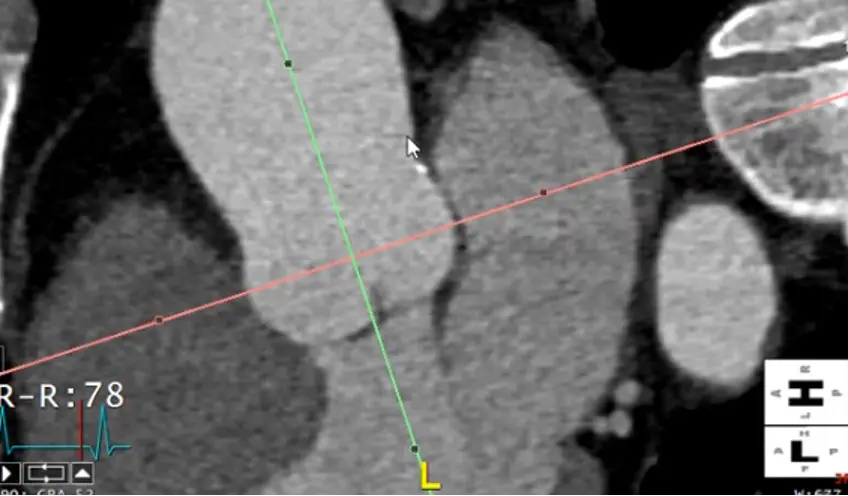

Measure at the widest segment

- The widest segment (typically) is at the mid-aorta at the level of the main pulmonary artery (MPA)

- Same as above, drag your crosshairs to the desired level and adjust to be perpendicular to the artery wall in the coronal and sagittal views. Line up the blue/green line to be in the center/parallel to the long axis of the aorta at that level.

- In the axial view, the âtrue short axisâ should appear like a circle

Alt+Dto auto-measure- Right click and

Captureto add this to theSeries List